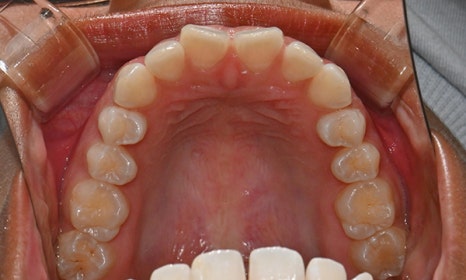

위아래 앞니 사이가 벌어져서 공간이 있었고, 앞니에 약간씩 배열이 틀어진 덧니가 있었습니다. 정면에서 보았을 때 윗니와 아래 앞니가 깊게 물려서 아래 앞니가 잘 보이지 않는 과개교합 양상을 보이고 있었습니다. 또한 왼쪽 아래 작은 어금니가 90도 앞으로 돌아가서 좌측 치아 배열 및 교합이 좋지 않은 상태였습니다.

초진시 구내사진 (2025. 3.31)

장치는 총 19개였으며, 아래 치아 배열은 12단계 안에 마무리 되었습니다. 아래 장치의 남는 7단계 동안 작은 어금니 배열을 조금이라도 맞추고 싶었으나, 시간적 제약 상 한 장치를 5일씩 착용하기로 하여서 짧은 기간 안에 치아 이동이 충분히 따라오기 힘들다고 판단하여 작은어금니 배열은 하지 않기로 하였습니다.

교정 마무리 후 사진으로 위아래 치아 배열이 개선되었고 공간이 모두 닫혔습니다. 위아래 앞니가 깊게 물리는 과개교합도 처음에 비하여 많이 개선되었습니다. 다만 아래 작은 어금니 배열로 인하여 왼쪽 어금니 교합은 아직 완벽하지 않은 상태로, 추후 본국으로 돌아가서 자료를 transfer 해드려서 이어서 치료를 받기로 하셨습니다.

위 오른쪽 앞니의 경우 초진시에도 틀어져있던 부위의 잇몸이 내려가 있었으므로, 치아가 배열되면 좌우 잇몸 높이가 맞지 않을 것임을 미리 고지시켜드렸었고, 추후 치은성형술로 잇몸 높이를 맞추는 것이 심미적으로 더 보기 좋을 것임을 추천드렸습니다.